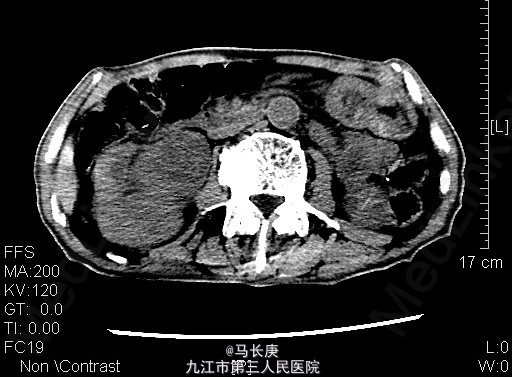

1、右上腹痛伴全程肉眼淡红血尿2月 2、患者于2月前无诱因出现右上腹痛伴全程肉眼淡红血尿,可以自行缓解,无血块、血条,无尿频、尿急、尿痛,无排尿困难,当时未引起重视,未去就医,7天前右上腹痛及血尿加重,于当地人民医院就诊,诊断为:右肾占位,现为进一步诊治于来我科进一步治疗。起病以来,一般情况尚可,近期体重明显下降。

3、查体:无明显异常 4、辅助检查:当地人民医院泌尿系CT平扫+增强:1.右侧输尿管结石2.右肾占位?(未见报告),我科fish(+)CTU:肾盂癌,侵蚀右肾包膜,左肾囊肿,慢性胆囊炎。双肾核素扫描:右肾GFR:9.5,左肾48.5

5、考虑右肾盂癌 6、入院后给予双肾核素扫描、CTU检查,考虑右肾盂癌,给予抗炎、补液、治疗。现病情平稳。 术前诊断:右肾盂癌、胆囊炎、左肾囊肿、右侧输尿管结石、贫血、低蛋白血症、胆囊炎,后行右肾癌根治术,手术顺利,术后恢复较好,术后病理示:肾恶性肿瘤(高分化肉瘤)。